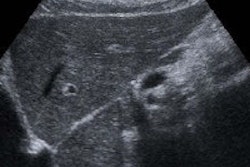

The review included 22 studies in the literature and assessed the utility of methods such as ultrasound and serial alpha-fetoprotein screening. The team of researchers, led by Dr. Devan Kansagara of Portland Veterans Affairs Medical Center, found that "the body of evidence on which current recommendations for screening are based has substantial shortcomings."

Two additional trials compared ultrasound screening intervals: One was a Taiwanese study that compared four-month and 12-month screening intervals in patients with serologic evidence of hepatitis B or C. Despite more patients in the four-month screening interval group having early-stage disease, survival rates were similar among both screening intervals. Furthermore, the "study had an unclear risk of bias because of poor reporting of outcome assessment and statistical analyses," they wrote.

The other trial, which had a low risk of bias, compared three-month and six-month ultrasound screening intervals, and found similar all-cause mortality rates among both groups.